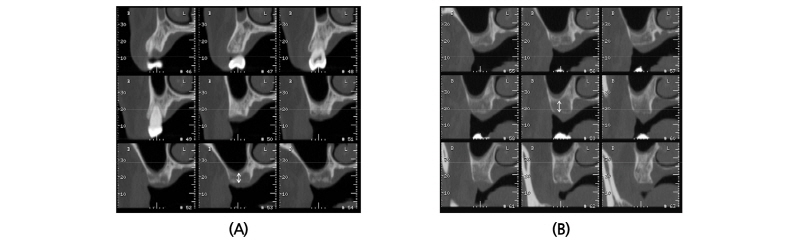

A 45-year old female patient who had missing teeth of first (#26) and second molar (#27) in left maxilla visited the clinic to plan for the reconstruction of both molars (Fig. 1). The edentulous ridge had sufficient buccopalatal width and the vertical dimension was about 8 mm from the soft tissue level (Fig. 1A, 1B). The patient was diagnosed as generalized chronic moderate periodontitis and received nonsurgical periodontal treatment prior to the surgery. In addition, regenerative therapy using bone graft materials was prepared in the intrabony defect of right mandibular first molar (#46). The missing maxillary molars were decided to be placed with implants and the panoramic view showed deficient RBH at #26 and #27 with sinus pneumatization (Fig. 1C). In computed tomography, RBH at #26 and #27 was measured to be 5 mm and 6 mm, respectively, and SFE spontaneously with implant placement using hybrid technique was planned (Fig. 2). Flap including the midcrestal incision and vertical incision at #25 distal line angle was reflected (Fig. 3A), and linear osteotomy was prepared with a piezoelectric device (Piezosurgery®, Mectron, Carasco, Italy) (Fig. 3B). Mesiodistal width of the osteotomy was about 10 mm to include both implantation site planned for #26 and #27, and was positioned about 7~8 mm from the crest paralleled along the sinus floor. Detachment of the Schneiderian membrane was limited in the internal surface of the floor and a serial drilling one step before the final diameter was done under the protection of the membrane with the sinus elevator inserted through the linear osteotomy site (Fig. 3C). Biphasic calcium phosphate (MBCP®, Biomatlante, Vigneux de Bretagne, France) of 0.5 g was grafted via lateral opening and pushed into the floor with osteotomes and final drilling was done. Straumann SLA® (Institute Straumann AG, Waldenburg, Switzerland) diameter 4.8 RN and 10 mm length implant was installed at both #26 and #27 (Fig. 3D). Non-submerged healing with healing abutment connection was done (Fig. 3E) and the stitches were removed after 10 days (Fig. 3F). Dome-shaped radiopacity surrounding the implant apex penetrated into the floor was shown immediately after the surgery (Fig. 4A) and the prosthetic delivery was done within 3 months of healing periods. Augmented sinus floor was maintained through the 6-year of follow-up (Fig. 4B).